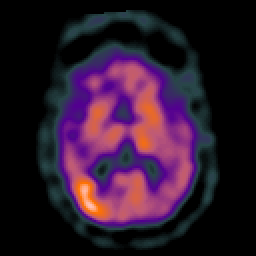

Subacute Stroke overlay -- Slice #12

[Home][Help][Clinical] Slice 12